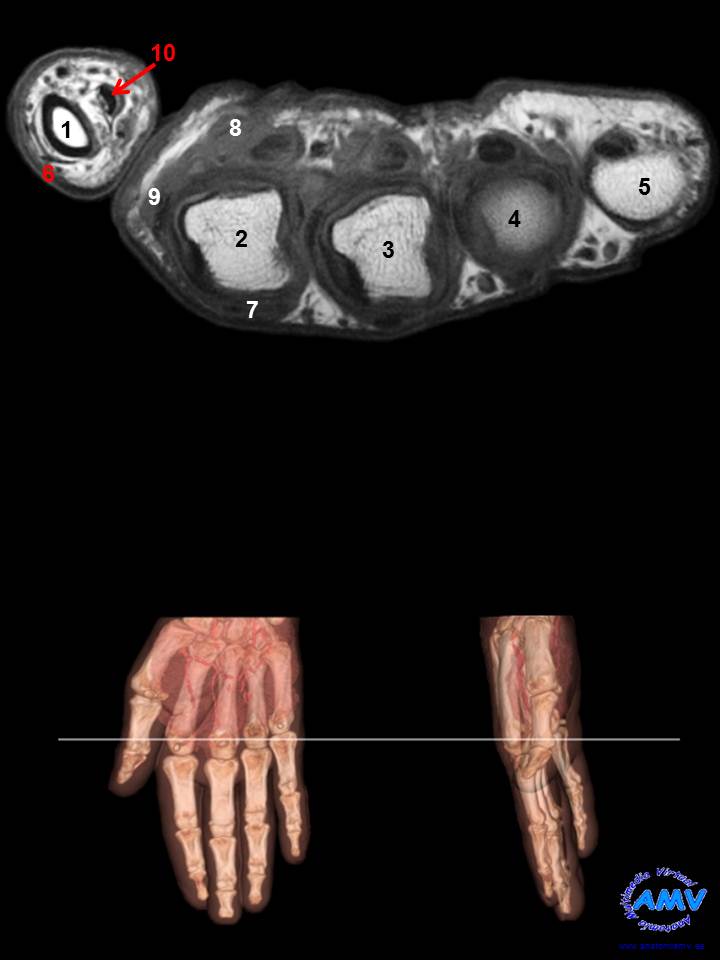

RMN Axial de Mano

ms_rmn_12.jpgIndique que estructura se señala con el número correspondiente:

El nº 1 señala a la .

El nº 2 señala a la .

El nº 3 señala a la .

El nº 4 señala a la .

El nº 5 señala a la .

El nº 6 señala al tendón del músculo .

El nº 7 señala al tendón del músculo .

El nº 8 señala al músculo .

El nº 9 señala al músculo .

El nº 10 señala al tendón del músculo .